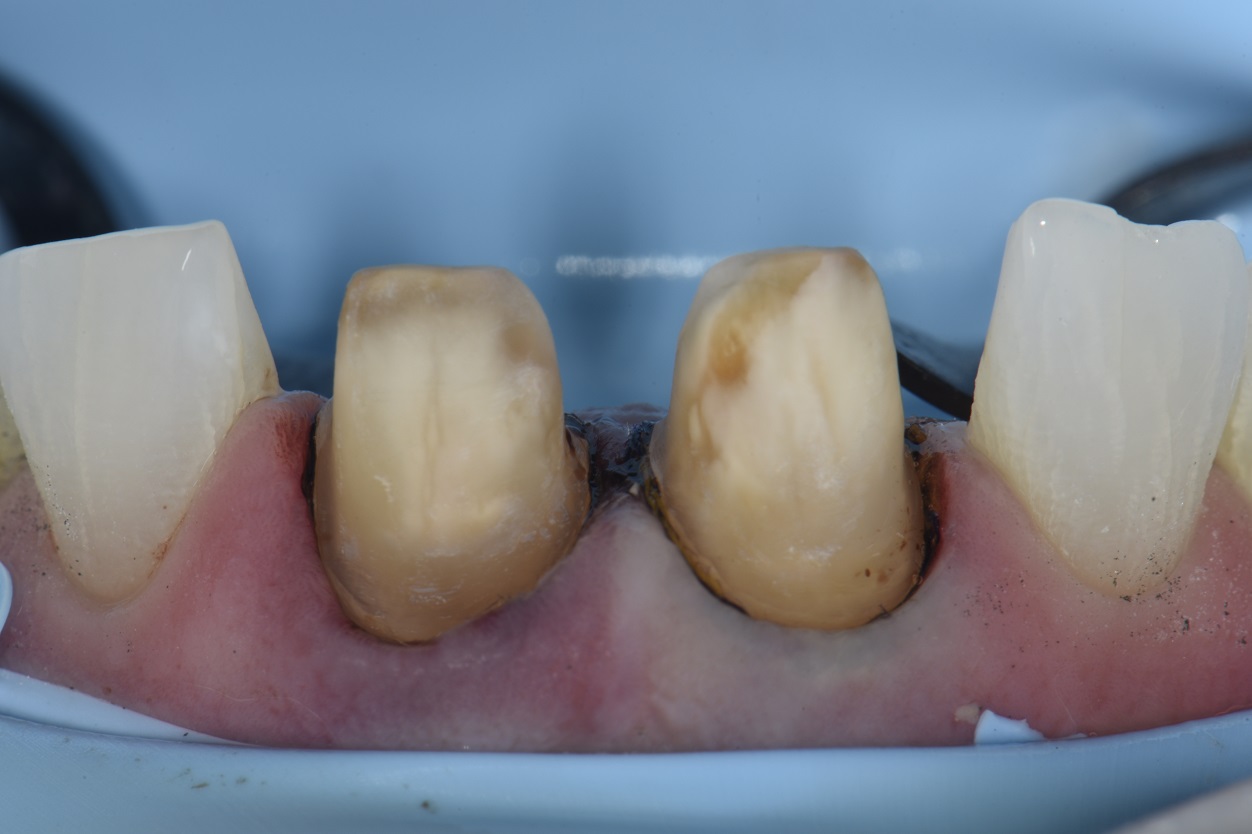

From www.clarencetam.co.nz

Removal of old crowns, immediate dentin sealing and resin coat How Do They Remove An Old Crown At times, the dentist may use the old crown if it is not severely damaged. Depending on a multitude of factors, that number will vary. An adhesive may also be used on the permanent crowns to weaken the cement. Understanding the temporary crown removal process. Options when performing root canal therapy for teeth that already have a dental crown. The. How Do They Remove An Old Crown.